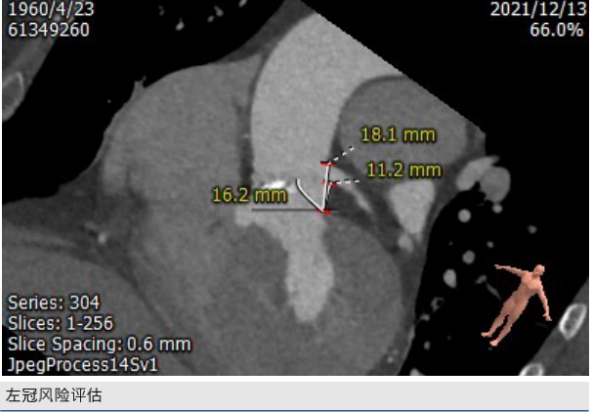

CT评估: